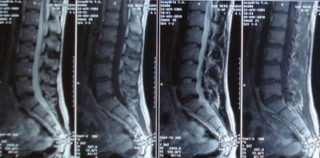

Снимок МРТ поясничного отела позвоночника

Чтобы достоверно определить происхождение и род дискомфорта в пояснице, при котором нередко отнимается, немеет нога, необходимо сделать визуализацию позвоночника. Для этого применяется рентген, компьютерная, магнитно-резонансная томография, позволяющие эффективно выявлять изменения. С целью оценки функционального состояния организма диагностика должна начинаться с лабораторных исследований.